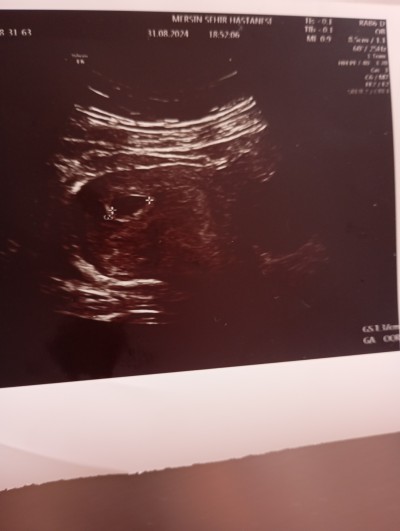

Kızlar kese var bebek yok dedi doktor 2gafta sinra gel dedi böyle olup bebeği görünen varmı kormu gekdi ya

Gebelik haftası 6